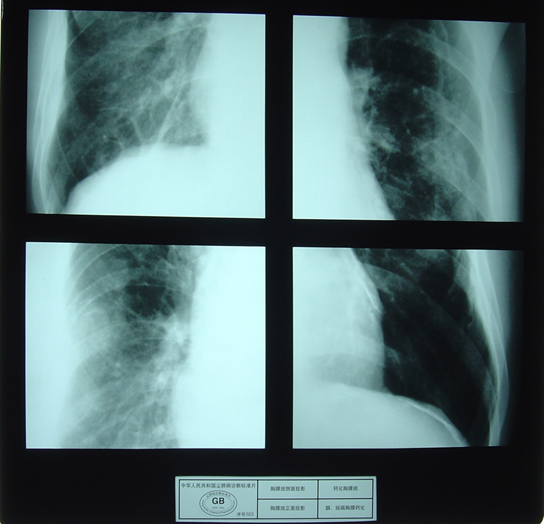

胸膜改变主要包括胸膜斑、胸膜增厚和胸膜钙化。胸膜斑:在X射线胸片上,肺野内除肺尖部和肋膈角区以外出现的厚度大于5mm的局限性胸膜增厚,或局限性钙化胸膜斑块。多见于两肺下侧胸壁6~10肋间,也可发生于膈胸膜和心包膜。弥漫性胸膜增厚的X射线影像呈不规则形阴影,以中、下肺区明显,有时可见点片或条状钙化影。

上图示胸膜斑侧面投影; 上图示钙化胸膜斑正面投影;

下图示胸膜斑正面投影; 下图示膈,纵膈胸膜钙化。

Asbestosispleural thickening